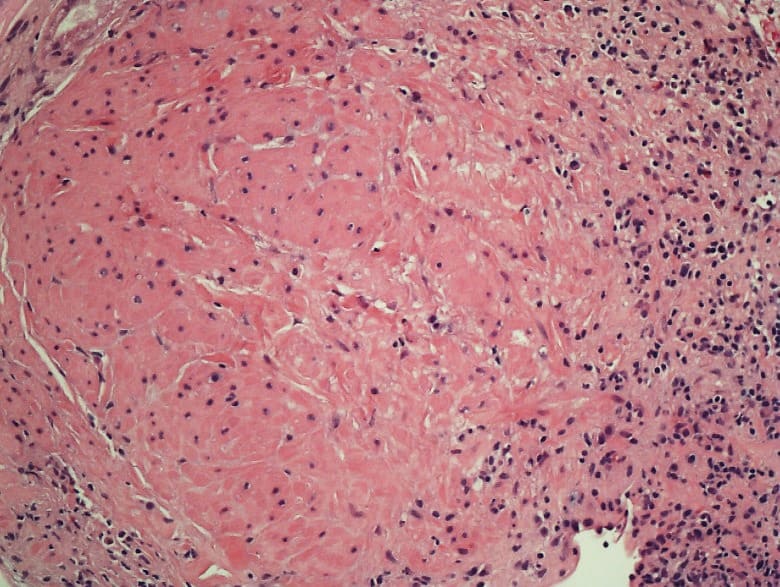

There was a small well circumscribed Leiomyoma which was reported as an incidental finding. Whorls of bland spindle cells lacking mitotic figures (Image 2, 3) were noted. Biopsy also showed hypertensive and diabetic nephrosclerosis of the vessels. Upon additional questioning, it was noted that the patient had stopped her immunosuppressive medications five months prior to this presentation with acute renal failure. She had received a living related donor renal transplant, 4 years ago with zero HLA mismatch. The donor and recipient were positive for EBV and Cytomegalovirus (CMV) antibodies. Post-transplant immunosuppression regimen consisted of Tacrolimus (calcineurin inhibitor) and Everolimus (mammalian target of rapamycin inhibitor, mTORi).

The histologic features of a Leiomyosarcoma are abundant mitotic figures, nuclear pleomorphism, and nuclear hyperchromatism that were not seen in our case.

Image 3: High resolution image: leiomyoma characterized by the absence of significant cytologic atypia and mitotic activity.